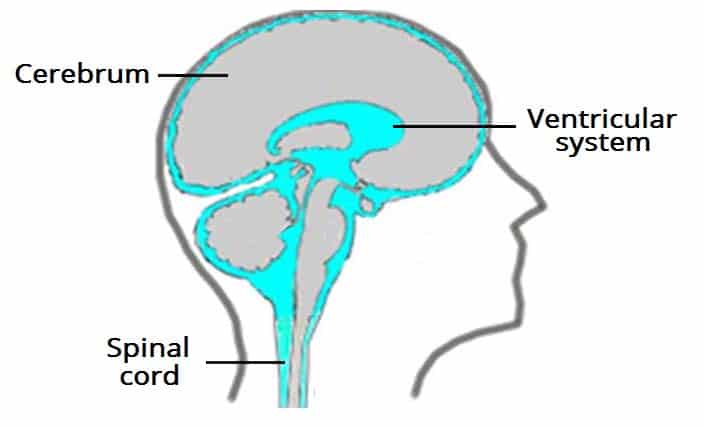

The ventricular system is a set of communicating cavities within the brain. These structures are responsible for the production, transport and removal of cerebrospinal fluid, which bathes the central nervous system. In this article, we shall look at the functions and production of cerebrospinal fluid, and the anatomy of the ventricles that contains it. Pro Feature - 3D Model You've Discovered a Pro Feature Access our 3D Model Library Explore, cut, dissect, annotate and manipulate our 3D models to visualise anatomy in a dynamic, interactive way. Learn More Functions of Cerebrospinal Fluid Cerebrospinal fluid is an ultrafiltrate of plasma that surrounds the brain and spinal cord. It serves three main functions: Protection – acts as a cushion for the brain, limiting neural damage in cranial injuries. Buoyancy – by being immersed in CSF, the net weight of the brain is reduced to approximately 25 grams. This prevents excessive pressure on the base of the brain. Chemical stability – the CSF creates an environment to allow for proper functioning of the brain, e.g. maintaining low extracellular K+ for synaptic transmission. By TeachMeSeries Ltd (2025) Fig 1Overview of the cerebrospinal fluid distribution in the brain Ventricles of the Brain The ventricles are structures that produce cerebrospinal fluid, and transport it around the cranial cavity. They are lined by ependymal cells, which form a structure called the choroid plexus. It is within the choroid plexus that CSF is produced. Embryologically, the ventricular system is derived from the lumen of the neural tube. In total, there are four ventricles – right and left lateral ventricles, third ventricle and fourth ventricle. Lateral Ventricles The left and right lateral ventricles are located within their respective hemispheres of the cerebrum. They have ‘horns’ which project into the frontal, occipital and temporal lobes. The volume of the lateral ventricles increases with age. By TeachMeSeries Ltd (2025) Fig 2Bird’s eye view of a cast of the ventricular system of the brain. Third Ventricle The lateral ventricles are connected to the third ventricle by the foramen of Monro. The third ventricle is situated in between the right and the left thalamus. The anterior surface of the ventricle contains two protrusions: Supra-optic recess – located above the optic chiasm. Infundibular recess – located above the optic stalk. Fourth Ventricle The fourth ventricle is the last in the system – it receives CSF from the third ventricle via the cerebral aqueduct. It lies within the brainstem, at the junction between the pons and medulla oblongata. From the 4th ventricle, the fluid drains into two places: Central spinal canal – bathes the spinal cord Subarachnoid cisterns – bathes the brain, between arachnoid mater and pia mater. Here the CSF is reabsorbed back into the circulation. By TeachMeSeries Ltd (2025) Fig 3The anatomical positioning of the ventricles of the brain. Production and Reabsorption of Cerebrospinal Fluid Cerebrospinal fluid is produced by the choroid plexus, located in the lining of the ventricles. It consists of capillaries and loose connective tissue, surrounded by cuboidal epithelial cells. Plasma is filtered from the blood by the epithelial cells to produce CSF. In this way, the exact chemical composition of the fluid can be controlled. Drainage of the CSF occurs in the subarachnoid cisterns (or space). Small projections of arachnoid mater (arachnoid granulations) protrude into the dura mater. They allow the fluid to drain into the dural venous sinuses. Learn more about the production and reabsorption of cerebrospinal fluid here. By TeachMeSeries Ltd (2025) Fig 4Coronal section of the skull, meninges and cerebrum. An arachnoid granulation is visible in the centre. Clinical Relevance Hydrocephalus Hydrocephalus is defined as an abnormal collection of cerebrospinal fluid within the ventricles of the brain. It is a serious condition, with chronic hydrocephalus causing raised intracranial pressure, and consequently cerebral atrophy. Based on the underlying cause, there are two clinical classifications: Communicating (Non-obstructive) Hydrocephalus – Abnormal collection of CSF in the absence of any flow obstruction in the ventricles. Common causes usually involve the functional impairment of the arachnoid granulations, such as fibrosis of the subarachnoid space following a haemorrhage. Non-communicating (Obstructive) Hydrocephalus – Abnormal collection of CSF, with flow obstructed within the ventricular system. The most common site of obstruction is the cerebral aqueduct, connecting the third and fourth ventricles. There is also a third classification, hydrocephalus ex vacuo – this refers to ventricular expansion, secondary to brain atrophy. This is often seen in patients with neurodegenerative conditions, such as Alzheimer’s disease. Treatment of hydrocephalus primarily involves reversing the cause. Whilst treating the cause, a shunt can be inserted, which drains the fluid into the right atrium or the peritoneum. By Lucien Monfils [CC-BY-SA-3.0-2.5-2.0-1.0], via Wikimedia Commons Fig 5Hydrocephalus on a CT scan. Do you think you’re ready? Take the quiz below Pro Feature - Quiz The Ventricles of the Brain Question 1 of 3 Submitting... Skip Next Rate question: You scored 0% Skipped: 0/3 1800 More Questions Available Upgrade to TeachMeAnatomy Pro Challenge yourself with over 1800 multiple-choice questions to reinforce learning Learn More Rate This Article